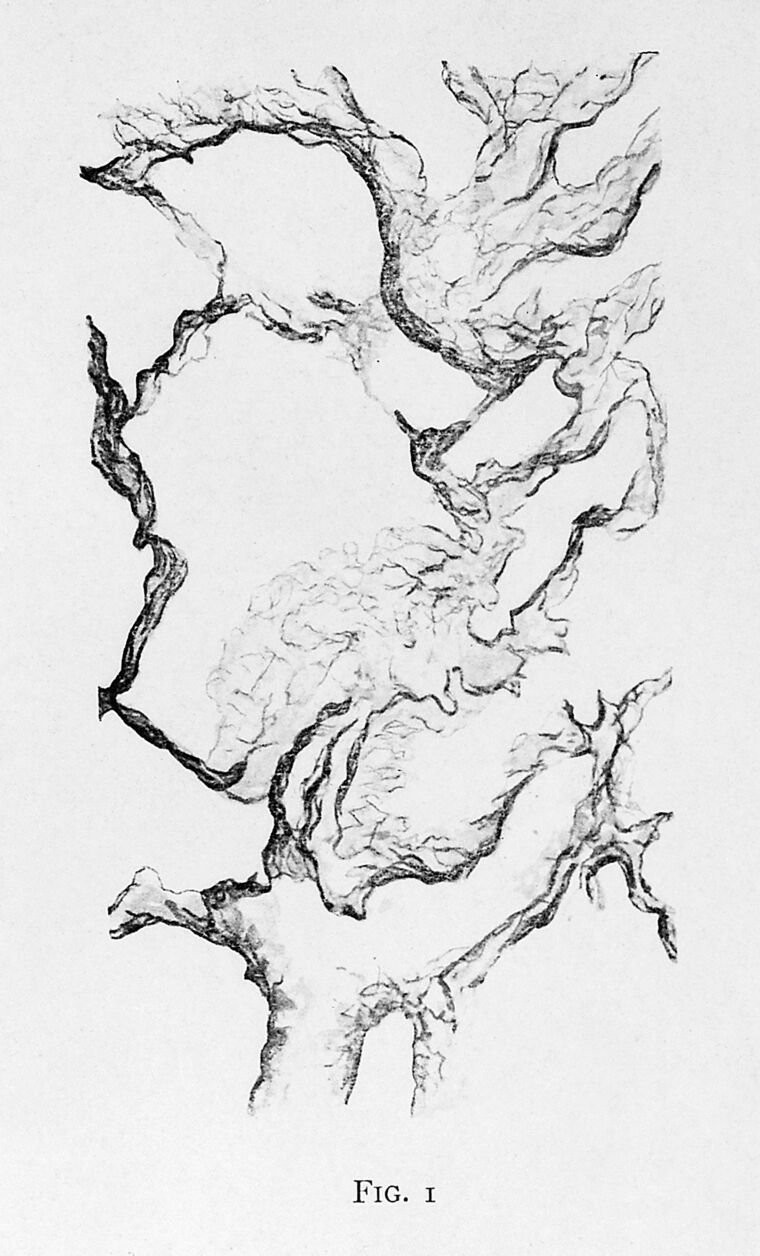

M0017177: Lung tissue stained with eosin, from Ruffer: Studies in the Palaeopathology of Egypt (1921)

Reproduction of a photomicrograph of lung tissue stained with eosin showing alveolar structure, published in Ruffer, Sir Marc Armand: Studies in the Palaeopathology of Egypt, Chicago: The University of Chicago Press, 1921. Related images: M0006275, M0009046, M0009048, M0009049, M0009050, M0009051, M0017178, M0017179, M0019338, M0019339, M0019340